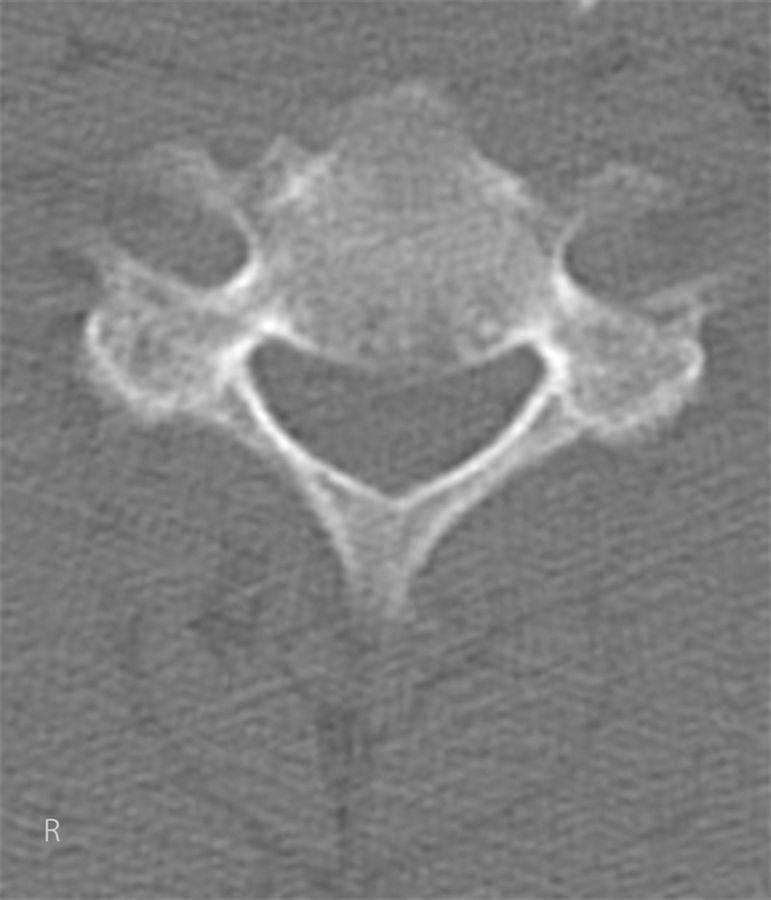

STEP 4 OPEN THE LAMINA: Open the lamina bilaterally and create a small hole in each one using a high-speed burr.

STEP 5 CREATE BONE STRUTS: Create bone struts from the spinous processes and tie them to each lamina.

步骤4打开椎板:双侧打开椎板,并用高速磨钻在每个椎板上制作一个小孔。

步骤5制作骨支柱:从棘突制作骨支柱并将其固定于每个椎板。